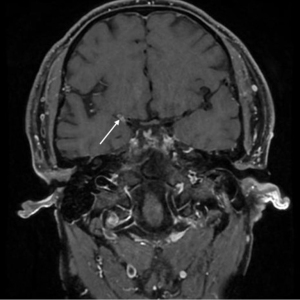

The HRMR-VWI protocol described was standardized across all 18 institutions and the quality assurance surveys were performed across centers. A 3.0-T magnetic resonance scanner (MAGNETOM Lumina 3.0T, Siemens Healthineers, Erlangen, Germany or 3.0T, Philips, Amsterdam, Netherlands) and a high-resolution 8-channel head/neck coil were used for magnetic resonance imaging (MRI) scanning. Lateral three-dimensional (3D) T1-weighted variable flip-angle spin echo sequence (3D-T1WI-SPACE) scans were performed before and after contrast agent administration under the following parameters: field of view (FOV) =180×180/173×199 mm2, layer thickness =0.6 mm, repetition time (TR) =25/21 ms, and echo time (TE) =3.5/3.6 ms. A contrast scan was performed 5 minutes after intravenous injection of gadolinium diethylene triamine penta-acetic acid (Gd-DTPA) contrast medium, and 3D time-of-flight magnetic resonance angiography (3D-TOF-MRA) was performed under the following parameters: FOV =180×180/173×199 mm2, layer thickness =0.6 mm, TR =25/21 ms, and TE =3.5/3.6 ms. All data was transmitted to the data center of Tsinghua University and image analysis is performed using the plaque analysis software independently developed by Tsinghua University School of Medicine, and included intraplaque bleeding, normalized wall index, degree of stenosis, plaque load, remodeling index, type of refactoring, and enhancement index (Figures 2,3). Standardized wall index = wall area/ (lumen area + pipe area). Plaque load = plaque area/total vascular wall area × 100%. Degree of stenosis = (stenosis diameter − normal diameter)/normal diameter. Intraplaque bleeding was a phenomenon of internal bleeding of atherosclerotic plaque, manifested as significant high signal shadows within plaques in both T1WI and TOF MRA sequences. The HRMR-VWI was read by an experienced neuroradiologist and if there was more than one plaque in the symptomatic territory, the culprit lesion was determined by two experienced neuroradiologists.